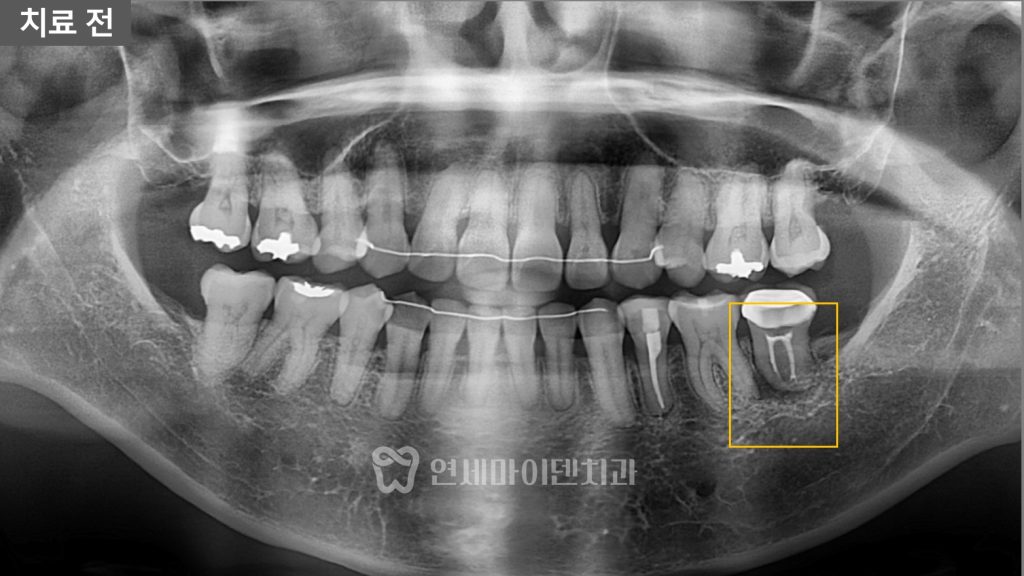

엑스레이를 확인해 보니

문제가 된 치아 뿌리 주변으로

J자 형태로 뼈가 녹아 있는 모습이

관찰되었습니다.

이러한 형태는 임상적으로

수직 치근 파절, 즉 치아 뿌리에 금이 간 경우에서

흔히 나타나는 양상이기 때문에

보철물을 제거했을 때

크랙이 확인된다면 발치 후 임플란트까지

고려해야 하는 상황이었습니다.